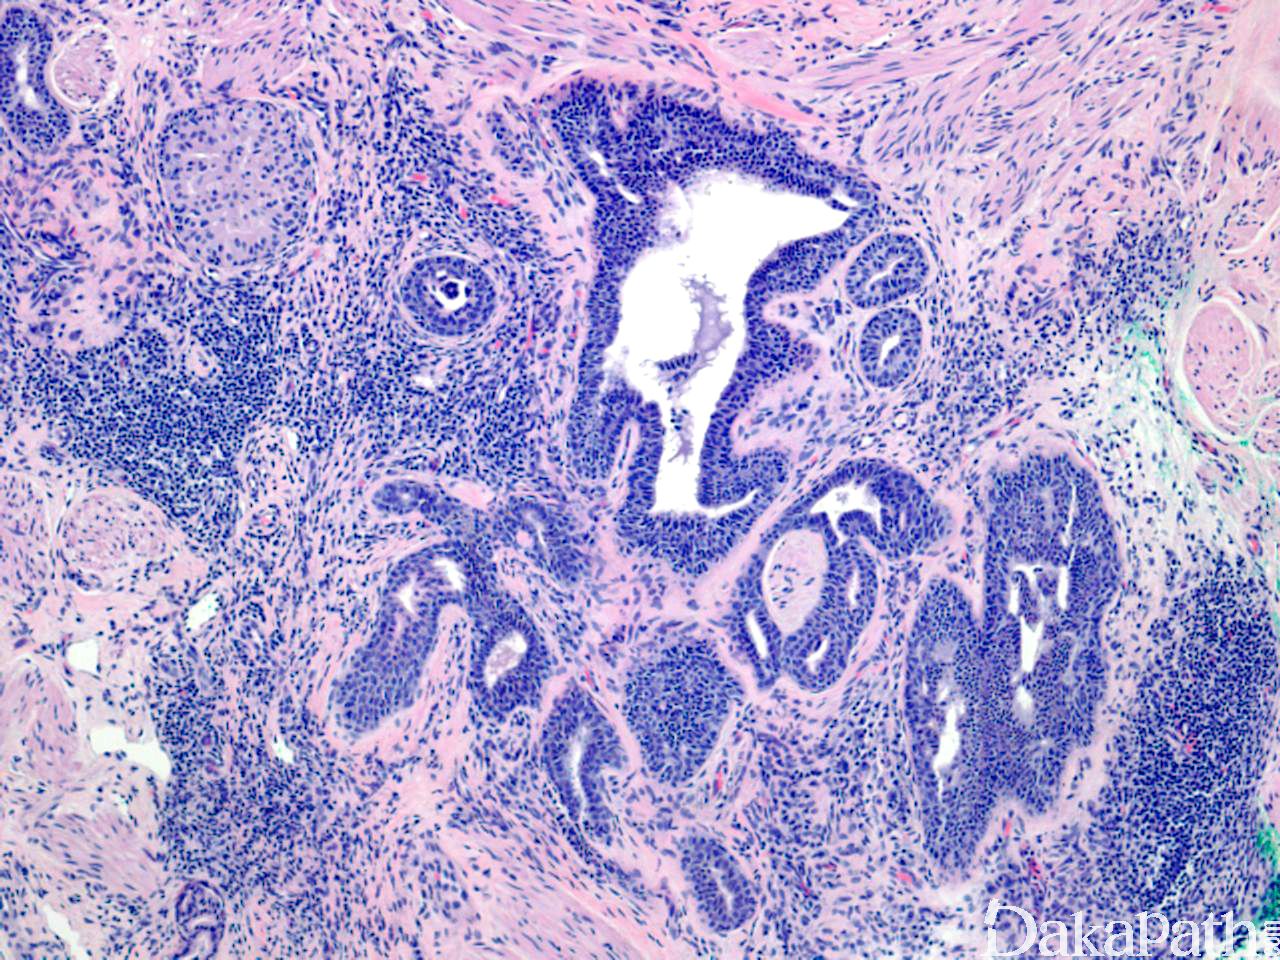

镜下见乳头下方真皮内边界清晰的小腺体增生,可呈结节样,与表皮相连;

腺腔样结构中导管上皮细胞增生形成乳头状突起,有时可见顶浆分泌;

腺体被覆两层细胞,内层为基底样细胞,细胞大小一致,核圆形,无异型性,为腺上皮细胞,腺上皮细胞可增生形成实性细胞巢或细胞索;外层是一层肌上皮细胞,胞浆淡染或透明;

无真正乳腺小叶间的基质。